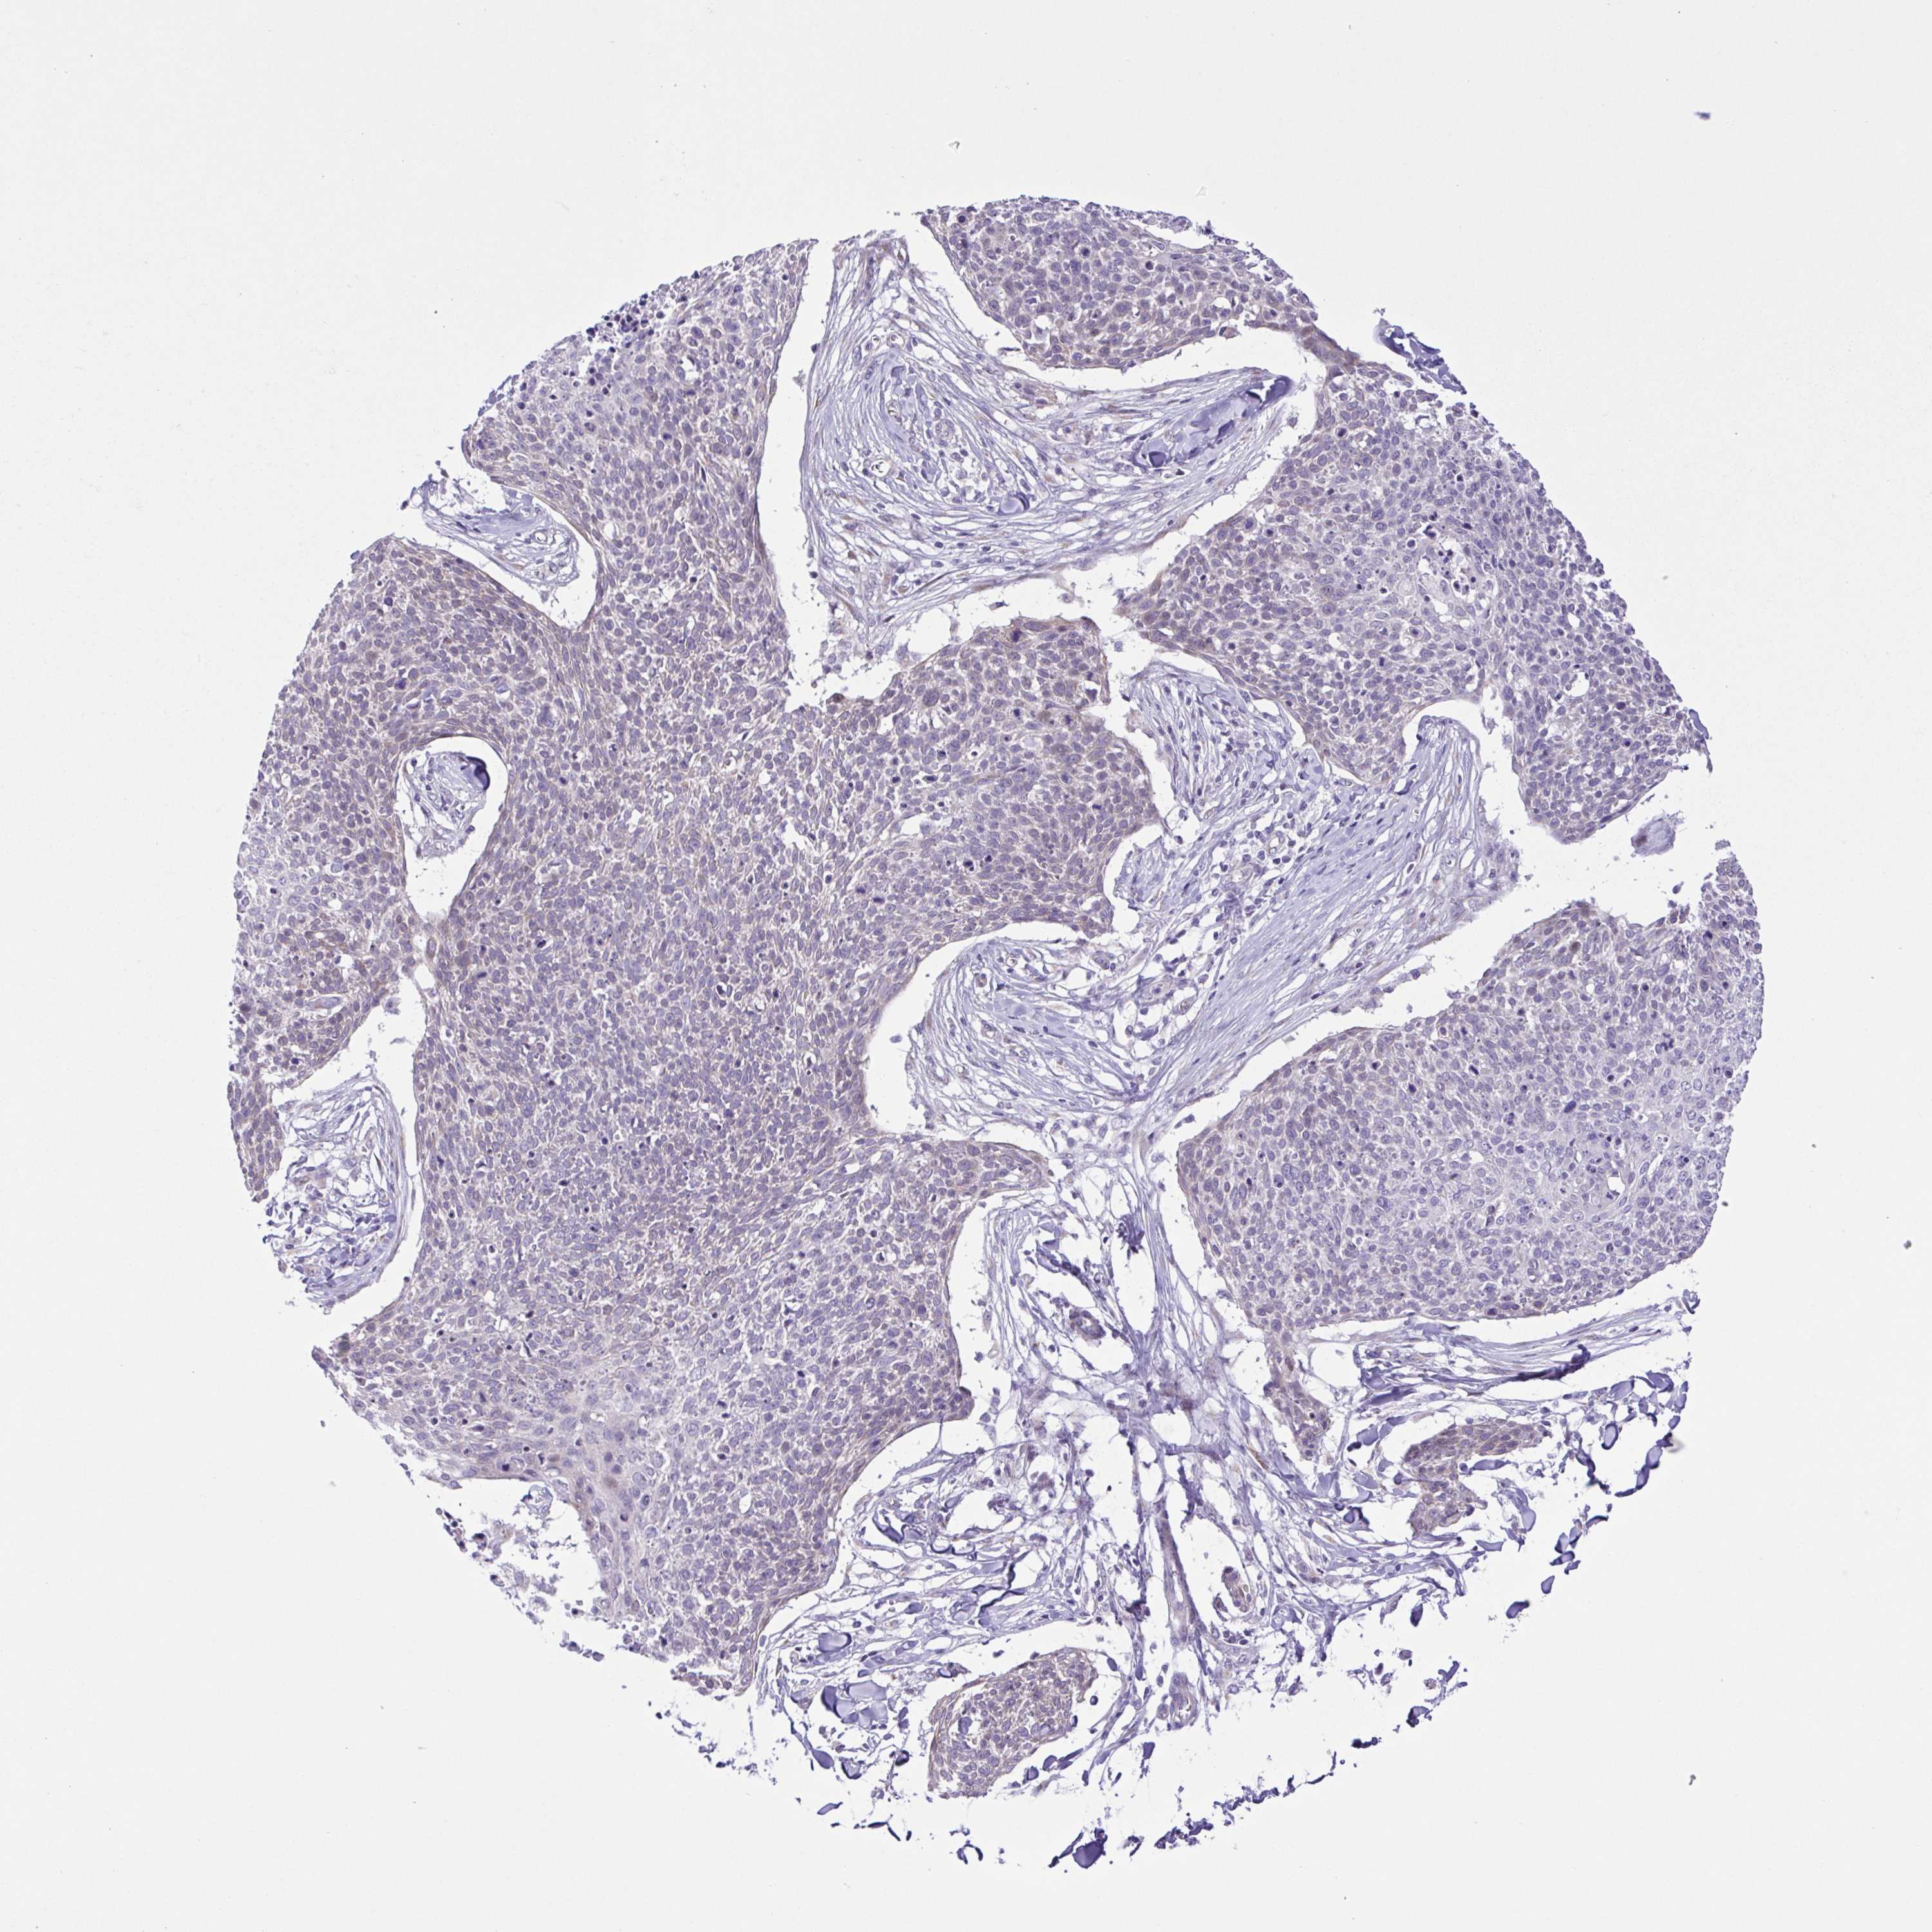

CANCER SKIN CANCER Show tissue menu

Basal cell and squamous cell cancer

SKIN CANCER - Protein expressioni

A mouse-over function shows sample information and annotation data. Click on an image to view it in a full screen mode. Samples can be filtered based on level of antibody staining by selecting one or several of the following categories: high, medium, low and not detected. The assay and annotation is described here.

Each image is clickable and will lead to virtual microscopy that enables deeper exploration of all samples and also displays staining intensity scores, fraction scores and subcellular localization as well as patient and tissue information for each sample.

Antibody HPA004728

Staining

High

Strong

Quantity

Location

Basal cell carcinoma

Squamous cell carcinoma, NOS